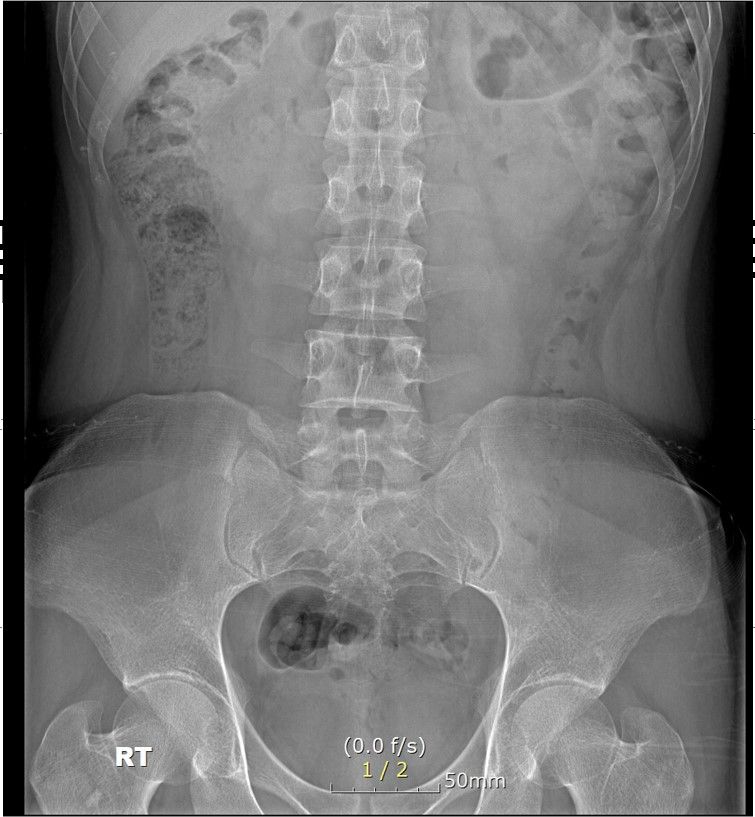

심할때는 1시간 걷다가 갑자기 골반과 옆구리가 알배기는듯이? 근육통이 심한듯이 느낌이와서 잠시 앉아서 쉬었습니다. ct영상으로도 디스크로 때문에 아프기엔 정상적인 정도라 하셔서 왜 아픈지 모르겠네요 . 현재 옆구리 좌,우 ,골반뒤쪽과 천추 꼬리뼈 또한 통증이 있으며 자고 일어나면 통증이 시작되고있습니다. 무엇때문인지 답답합니다. CT또한 촬영 했습니다.

x ray에 통증있는부분 표시 했습니다. 주로 뒤쪽으로 아픕니다. 3개월 됬습니다...직업상 앉아있는시간이 많습니다.